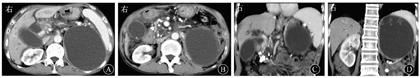

血常规WBC计数为2.74×109/L,RBC计数为3.12×1012/L,PLT计数为84×109/L。血清淀粉酶为112 U/L,胆红素水平正常。肿瘤标志物:AFP正常,CEA为11.07 μg/L,CA19-9为205.50 kU/L,CA125为116.90 kU/L。HBsAg为172.62 mIU/mL,其他乙型肝炎标志物均正常。2016年6月24日,上腹部CT平扫和增强(图1)示:①胆系扩张,胆总管下段有软组织密度影并强化,需考虑占位可能;②胆总管下段多发结石;③慢性胰腺炎并胰管明显扩张;④胆囊结石并胆囊炎;⑤肝硬化;⑥左肾结石,左肾巨大囊肿。MRI和MRCP检查(图2)示:①胆总管下段结石并胆系扩张;②胆总管下段狭窄,需排除占位;③左肾区巨大囊肿。7月2日行内镜下逆行胰胆管造影术(endoscopic retrograde cholangiopancreatography,ERCP),内镜显示食管静脉曲张(重度),胆管造影示胆总管中段明显狭窄,狭窄处长约2.0 cm,狭窄以上肝外胆管扩张,术中胆管腔内超声(intraductal ultrasonography,IDUS)检查狭窄处胆管未见明显异常,造影未见明确结石影,沿胆总管导丝置入覆膜金属支架于狭窄处。7月7日泌尿系统多普勒超声检查示左肾窝异常回声团块,考虑左肾囊肿可能。7月9日计算机断层扫描泌尿系统延时成像(computed tomographic urography,CTU)(图3)示:左肾区囊性病灶未见造影剂进入,提示假性囊肿形成可能性大。7月20日肝脏静脉血管造影(computed tomographic venography,CTV)(图4)示:肠系膜上静脉血栓形成,门静脉主干起始处闭塞,门静脉海绵样变性。8月1日复查CT增强(图5)示:①肝内胆管扩张、胆总管内置管术后改变。②慢性胰腺炎;胰尾囊肿引流术后,囊腔内积气。

消化科何文华主治医师:患者为男性,病程长,主诉上腹部胀痛2月余入院,体格检查以上腹部痛为甚。外院上腹部MRI和MRCP检查显示胆总管下段狭窄并胆、胰系梗阻,胆总管下段多发结石,所以考虑腹痛为胆系结石所致,而胆总管下段管腔狭窄可能为炎性狭窄,患者无黄疸、发热,提示胆管未完全梗阻,可择期行ERCP取出胆总管结石并放置支架。复查CT显示胆总管下段有软组织密度影,且患者肿瘤标志物CA19-9升高,不能排除恶性病变所致的胆系梗阻,可行IDUS检查,必要时行细针穿刺以排除恶变。患者有慢性腹泻表现,既往有长期饮酒史,CT检查亦提示慢性胰腺炎,故诊断慢性酒精性胰腺炎明确。患者的胰尾囊性占位结合其慢性胰腺炎,需考虑胰腺假性囊肿的可能,但CT检查结果考虑左肾巨大囊肿,可请泌尿外科会诊。在诊治上应首先确定胆总管下段狭窄的性质,处理胆道梗阻,以缓解上腹痛症状。

影像科余晨主治医师:成人胆总管狭窄可继发于各种良恶性病变,拥有广泛的病因疾病谱。良性狭窄的病因包括医源性胰腺炎、急性或慢性胰腺炎、胆总管结石、原发性硬化性胆管炎、IgG4相关硬化性胆管炎、肝移植、复发性化脓性胆管炎、Mirizzi综合征、获得性免疫缺陷综合征相关胆管疾病和Oddi括约肌功能障碍等。恶性狭窄的病因包括胆管上皮癌、胰腺癌和壶腹周围癌。少见的病因包括胆道炎性假瘤、胆囊癌、肝癌、胆道转移癌、肝门部或胰周淋巴结肿大压迫继发胆系扩张[1]。影像学检查尤其是MRI平扫和增强与MRCP,是鉴别胆系梗阻病因较为理想的无创性方法。既往研究表明,恶性病变引起的胆道梗阻相较于良性病变更易出现以下倾向:首先,恶性病变所致的胆管壁增厚程度较良性病变更明显,病变累及范围更广,其上游胆管扩张也更为明显;其次,胆管恶性病变强化较良性病变更为明显,持续时间也更久[2];再次,胆管恶性病变在弥散加权成像(diffusion weighted imaging,DWI)上表现为更高的信号,提示其弥散受限程度更高[3];最后,胆管恶性病变更多表现为胆道偏心性狭窄,并且增厚管壁的内外缘更加毛糙、不光整[1]。综合患者在南昌大学第一附属医院的MRI和MRCP检查,首先,胆管狭窄位于胆总管下段,局部胆管壁增厚程度虽较明显,但累及长度较短,其上游胆管虽明显扩张,但其扩张程度与狭窄上方的结石直径相仿,故考虑其扩张原因应更多地归咎于狭窄上方的结石;其次,胆总管下段狭窄处管壁呈环形对称性增厚且管壁外缘较光整、轻中度强化;最后,DWI图像上的病灶信号不高,且肝门区未见明显恶性肿大淋巴结。以上这些影像学表现并不符合恶性病变的影像特征,故考虑胆总管下段梗阻为良性炎性病变所致,以慢性胰腺炎所引起的胆总管下段炎性狭窄的可能性最大。另外,患者胰胆管同时明显扩张,需要与胰头癌或壶腹周围癌所致的"双管征"进行鉴别诊断,患者胰管明显扩张的同时可见胰管钙化灶和胰腺结石影,提示胰管扩张为慢性胰腺炎所致,而并非由胰胆管共同开口处的病变所致。CA19-9升高虽常见于胰胆管和胃、肠道来源的恶性肿瘤,但低浓度增高和一过性增高亦可见于慢性胰腺炎、胆石症、肝硬化、肾功能不全、糖尿病等,故建议在治疗期间随诊复查该项指标。

泌尿外科张成主治医师:患者上腹部CT平扫和增强显示左肾结石;左肾实质见一巨大无强化囊性占位,由于囊肿与肾实质无显著分界,首先要考虑左肾巨大囊肿,其次囊肿与胰尾也紧密相连,与胰腺假性囊肿难以鉴别。建议完善左侧逆行肾盂造影或CTU,若明确诊断为左肾囊肿后,可转泌尿外科进行手术治疗。